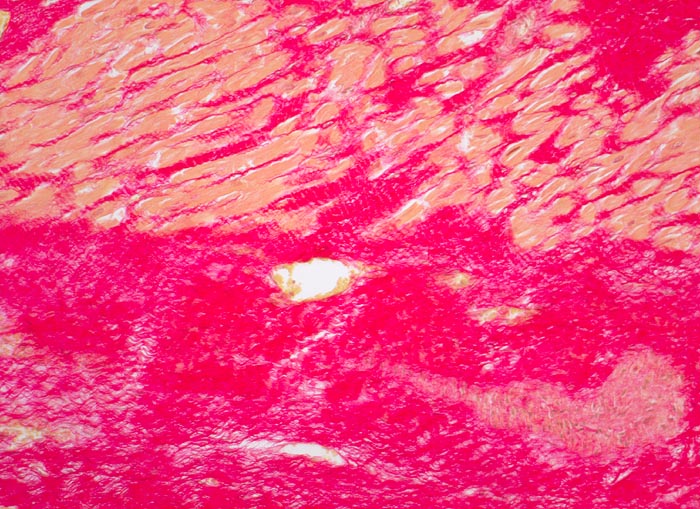

PathoPic – image database / PathoPic ID 4628 - Myokardinfarktnarbe

Myokardinfarktnarbe

Abschnitte der Muskulatur ersetzt durch siriusrote, wellige Kollagenfaserbündel (Kollagen Typ I). In den Ausläufern der Narbe perizelluläre Fibrose um das überlebende Myokard. Stellenweise in Narbenfeldern noch weite Kapillaren. Fokal zellreicherer Narbenabschnitt mit Fibroblasten/-zyten.

Schwere stenosierende Sklerose der rechten Koronararterie. 4x5cm grosse Narbe im Bereich der Hinterwand.

Diabetes mellitus. St.n. Hinterwandinfarkt vor 3 Jahren

100